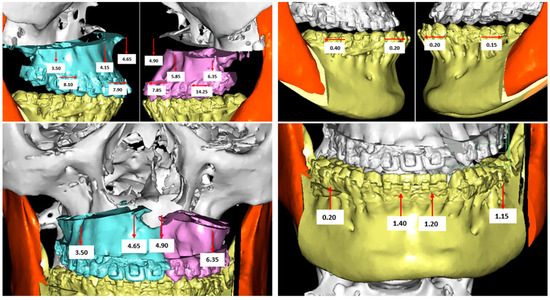

2.1. Digital Surgical Planning

2.2. Evaluation of the Surgical Accuracy